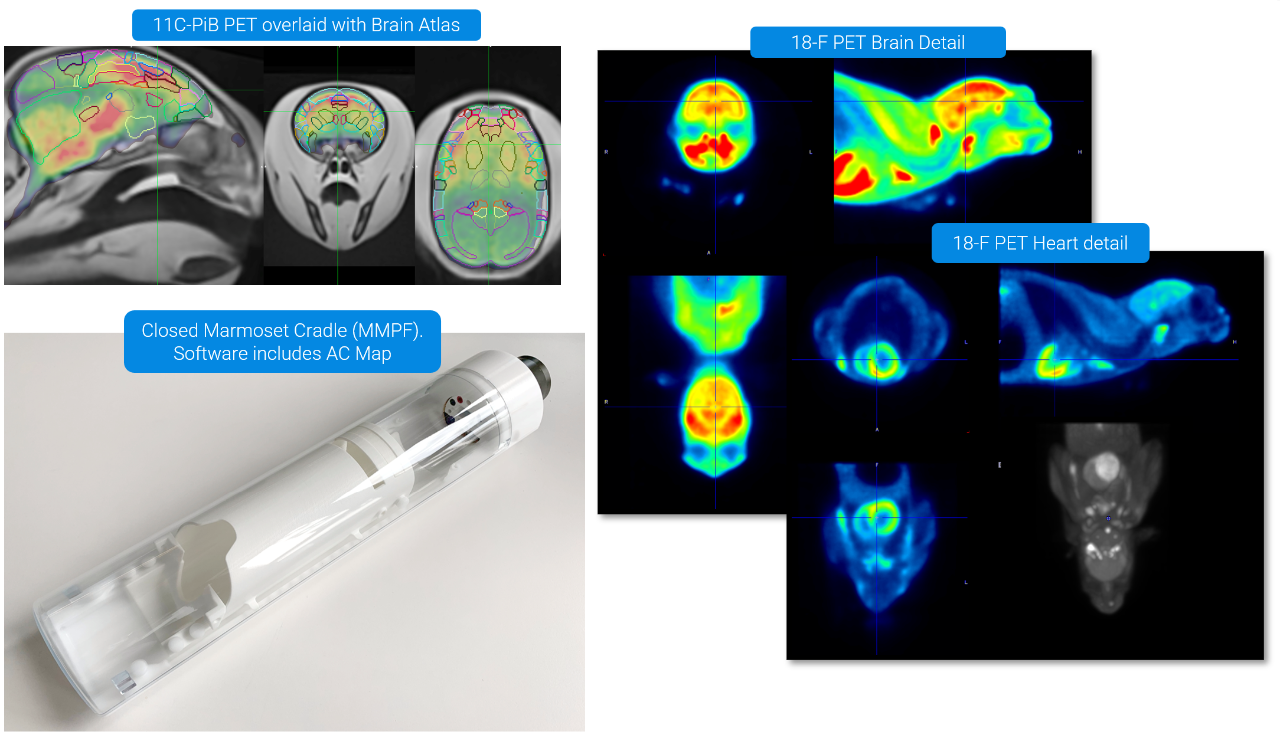

AD Model in Marmosets: Awake Imaging with 11C-PiB and 18F-FDG PET